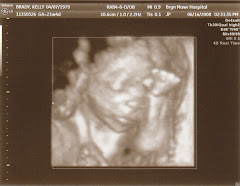

Marcelo has now been home for 2 days and he loves his pad. Kelly is a natural at the mom thing and I'm starting to master the art of the diaper change (although earlier today Kelly was the unfortunate recipient of an errant spray - HA!). My mom, who immediately flew up from Miami, has been a tremendous help too. I know I'm biased but this kid has to be the coolest newborn ever. We've received a ton of calls, texts and emails. I personally have not been able to get back to everyone and I apologize for that. We've also received many request to post more pictures, so here it is...Still in labor...